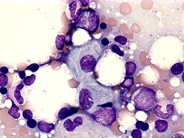

Gaucher’s disease - 1.

Gaucher cells are macrophages containing cerebrosides.